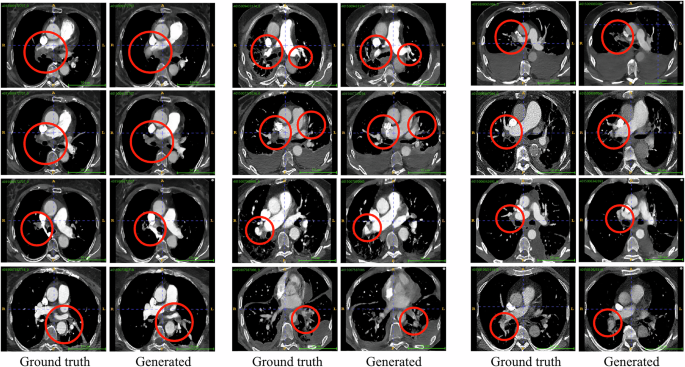

In Fig. 2, we show visual examples of generated scans. The results demonstrate that the generated scans seem anatomically correct, realistic and consistent between sequential slices. Figure 2 visualizes key slices from four randomly selected generated samples from our held-out test set and the corresponding slices compared with the ground truth scan. As can be seen, the slices are similar, but small variations exist compared to the ground truth samples. These differences will be further discussed in the following sections. In addition, the input CXRs for the generated samples are depicted, along with the corresponding coronal example slice from the ground truth and the matching slice from the generated sample. It is evident that the general anatomical structure is preserved between the generated sample and the ground truth and matches the CXR input.

We show examples of CXR to 3D CTPA Generation with an X-ray2CTPA model. Shown are four randomly selected generated 3D-CTPA samples from the test set, synthesized from a 2D CXR input. We compare slices from the generated 3D-CTPA scan to the ground truth samples. For simplicity, we present five key slices from the whole 3D-scan. The input CXR is presented as well, along with its matching coronal slice from the matching CTPA and generated 3D-CTPA. Note: throughout the paper the axial CT images appear slightly deformed. This is due to the preprocessing of the data and region of interest selection. (We elaborate on this in the Dataset Section).

We next compare generated PE examples from the synthesized data with their corresponding ground truth. Figure 3 presents the results. As observed, the X-ray2CTPA model successfully generates findings consistent with PE diagnosis. Although some variations in manifestation and location may occur in the generated PE findings compared to the ground truth samples, the overall results are similar. We hypothesize that our model captures the statistical essence of the ground truth, even if the resulting scans are not identical. This hypothesis is supported by the results presented in the following sections.